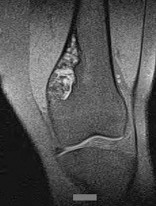

A 15-year-old male presents with deep knee pain awakening him at night. Radiographs show a permeative destructive lesion in the distal femoral metaphysis with a 'sunburst' periosteal reaction and Codman's triangle.

Biopsy confirms high-grade conventional osteosarcoma. What is the most critical prognostic factor for long-term overall survival in this patient?

Explanation

For localized high-grade osteosarcoma, the most important prognostic indicator is the histologic response to neoadjuvant chemotherapy. This is evaluated during the definitive resection. A 'good response' is typically defined as greater than 90% or 99% tumor necrosis. Patients who achieve this level of necrosis have a significantly improved disease-free and overall survival rate compared to 'poor responders' who have extensive viable tumor cells remaining.